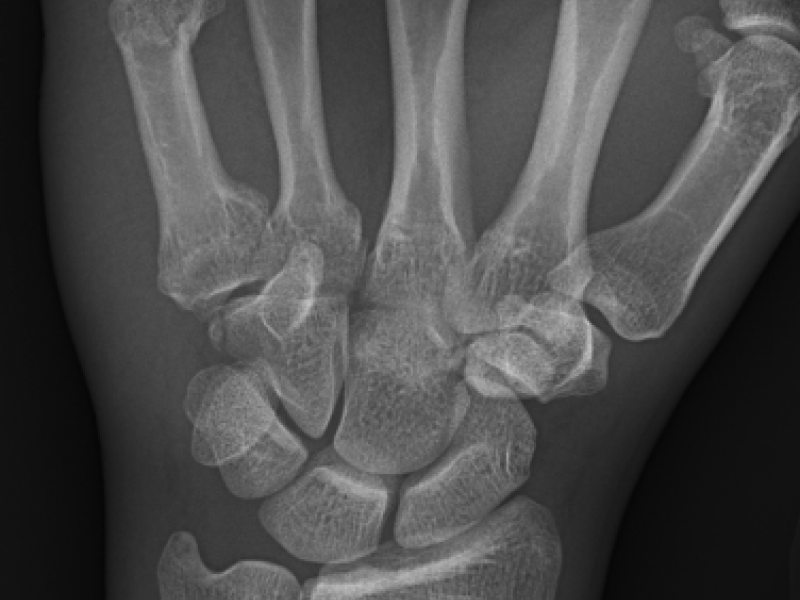

What's the diagnosis? By Dr. Erica Schramm

A 45 year old male presents for pain and swelling in his